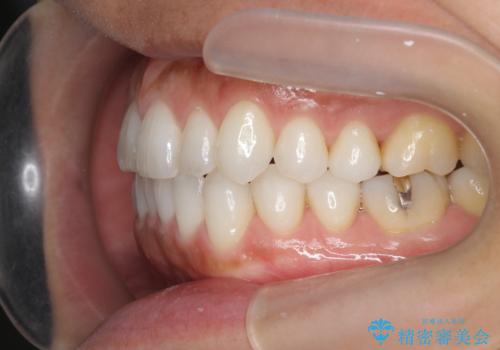

30代女性 前歯のがたつき

- 30代女性

- 矯正装置

- インビザライン

- 治療期間

- 1年5ヶ月

- 前歯のがたつきを主訴に来院。

右下の奥の銀歯も治療しています。

下の前歯を下げるため、IPR(歯をわずかに削る処置)を行っています。